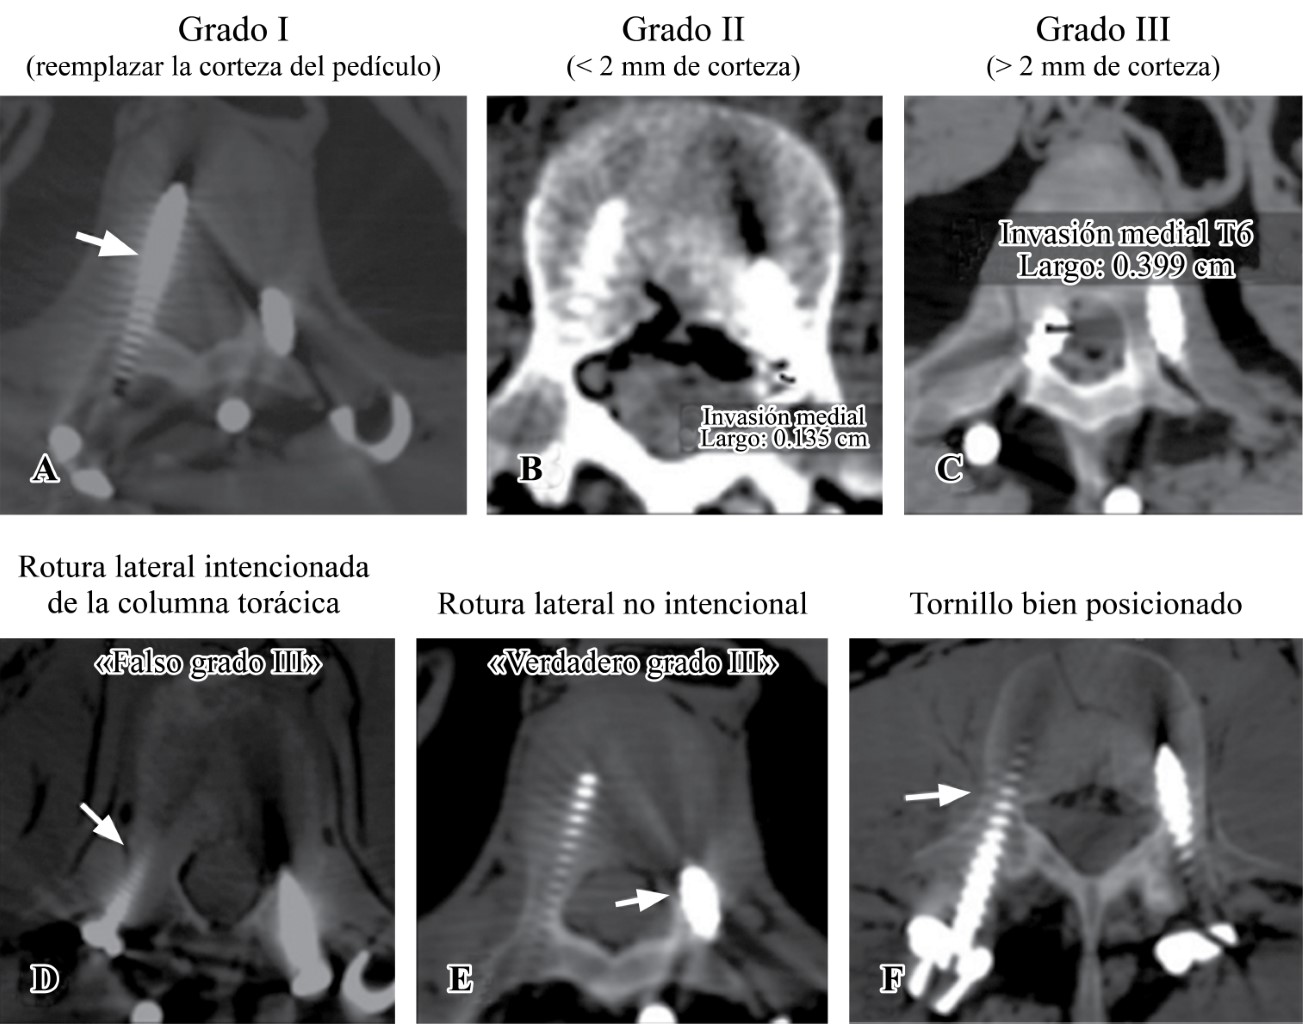

Introduction: Scoliosis is a complex deformity that affects all three planes of the axis of the spine. The association between neuromuscular pathology and vertebral alignment was initially described in 1960. Neuromuscular pathology is progressive and results in postural abnormalities. Surgical goals in patients with neuromuscular deformity include anatomical correction for sedation and ambulation, as well as functional improvement. The gold standard of treatment is by posterior approach with transpedicular screws. The "hands-free" technique saves surgical time, decreases radiation by reducing the use of fluoroscopy. The advent of 3D printing technology allows precise study of the anatomical area and detail of the deformity in its three planes. This model can be sterilized for transoperative guidance. A 13-year-old female patient who develops thoracolumbar neuromuscular scoliosis secondary to spastic cerebral palsy (CP), with previous instrumentation T11-L3 of which he develops severe proximal curve. After the segmentation of the three-dimensional model, pedicle violation greater than 2 mm towards bilateral medullary canal was detected in the pedicles of L1 and L2 of previous instrumentation, pedicle dysplasia and the morphological characteristics of the pedicles were observed. Three-dimensional planning and the use of surgical guides represent a tool for surgical planning, especially in severe cases and with pedicle dysplasia. It helps as a surgical guide for the placement of hands-free transpedicular screws with possible reduction of radiation and anesthetic time.

Figure 3

Figure 4